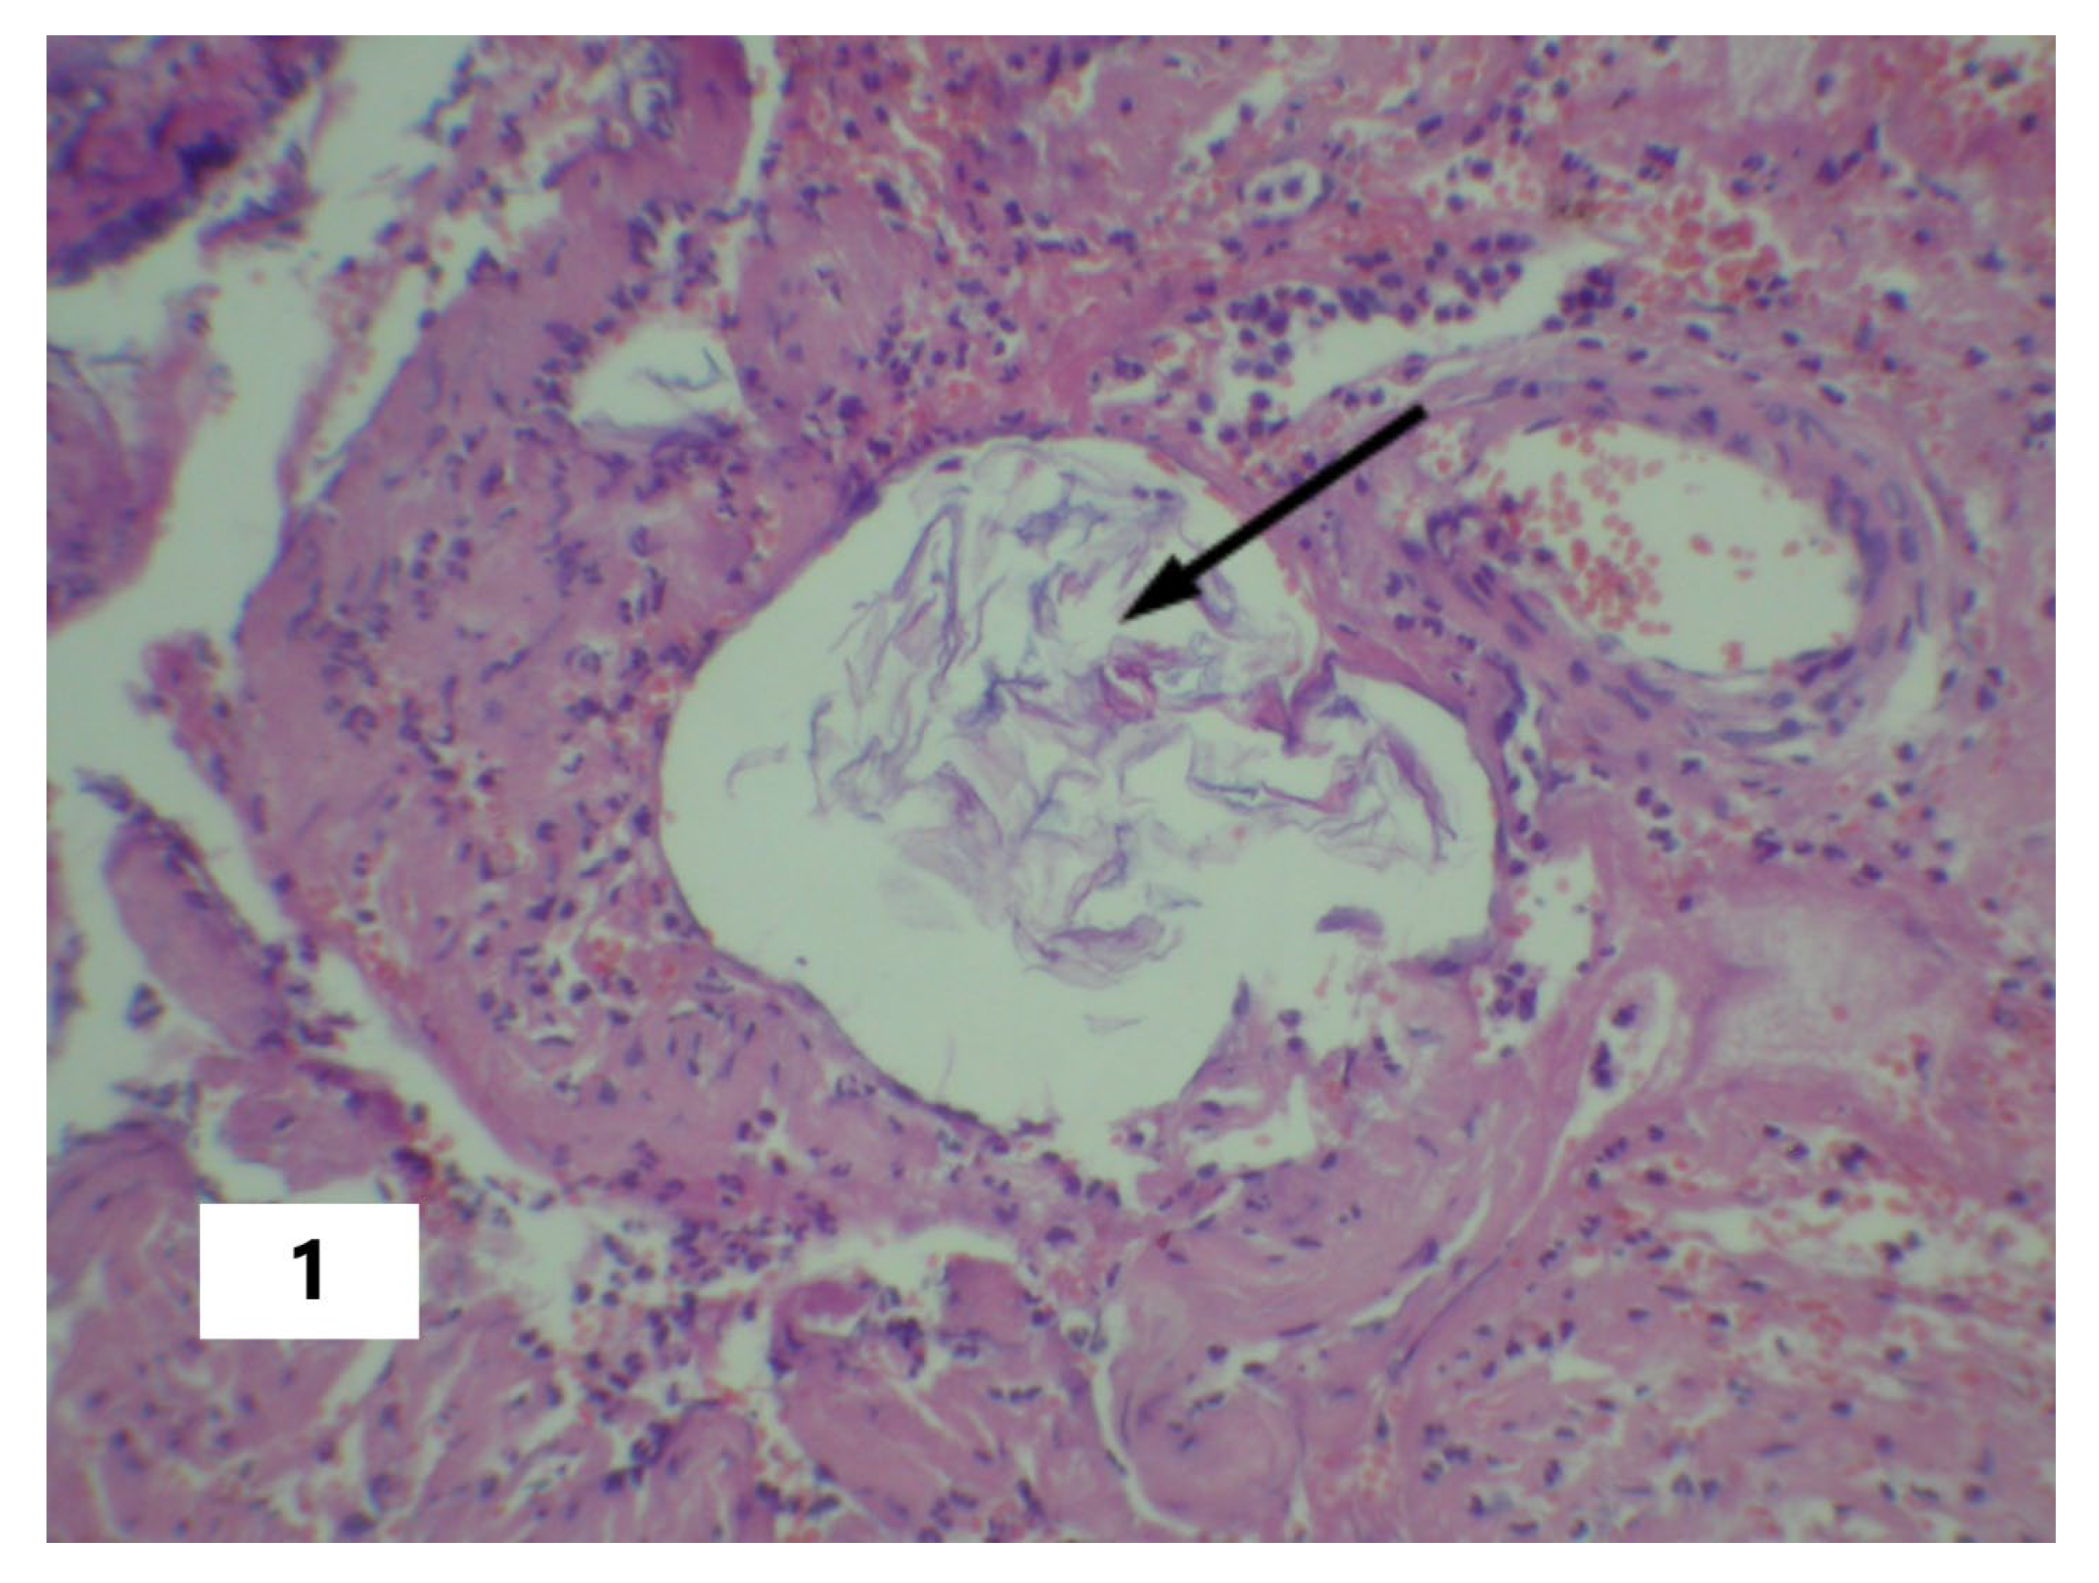

| Fetal squamous cells in the maternal pulmonary circulation | yes | no | yes | yes |

| Multiple fibrin clots in the microvasculature of the lungs and liver | yes | no | yes | yes |